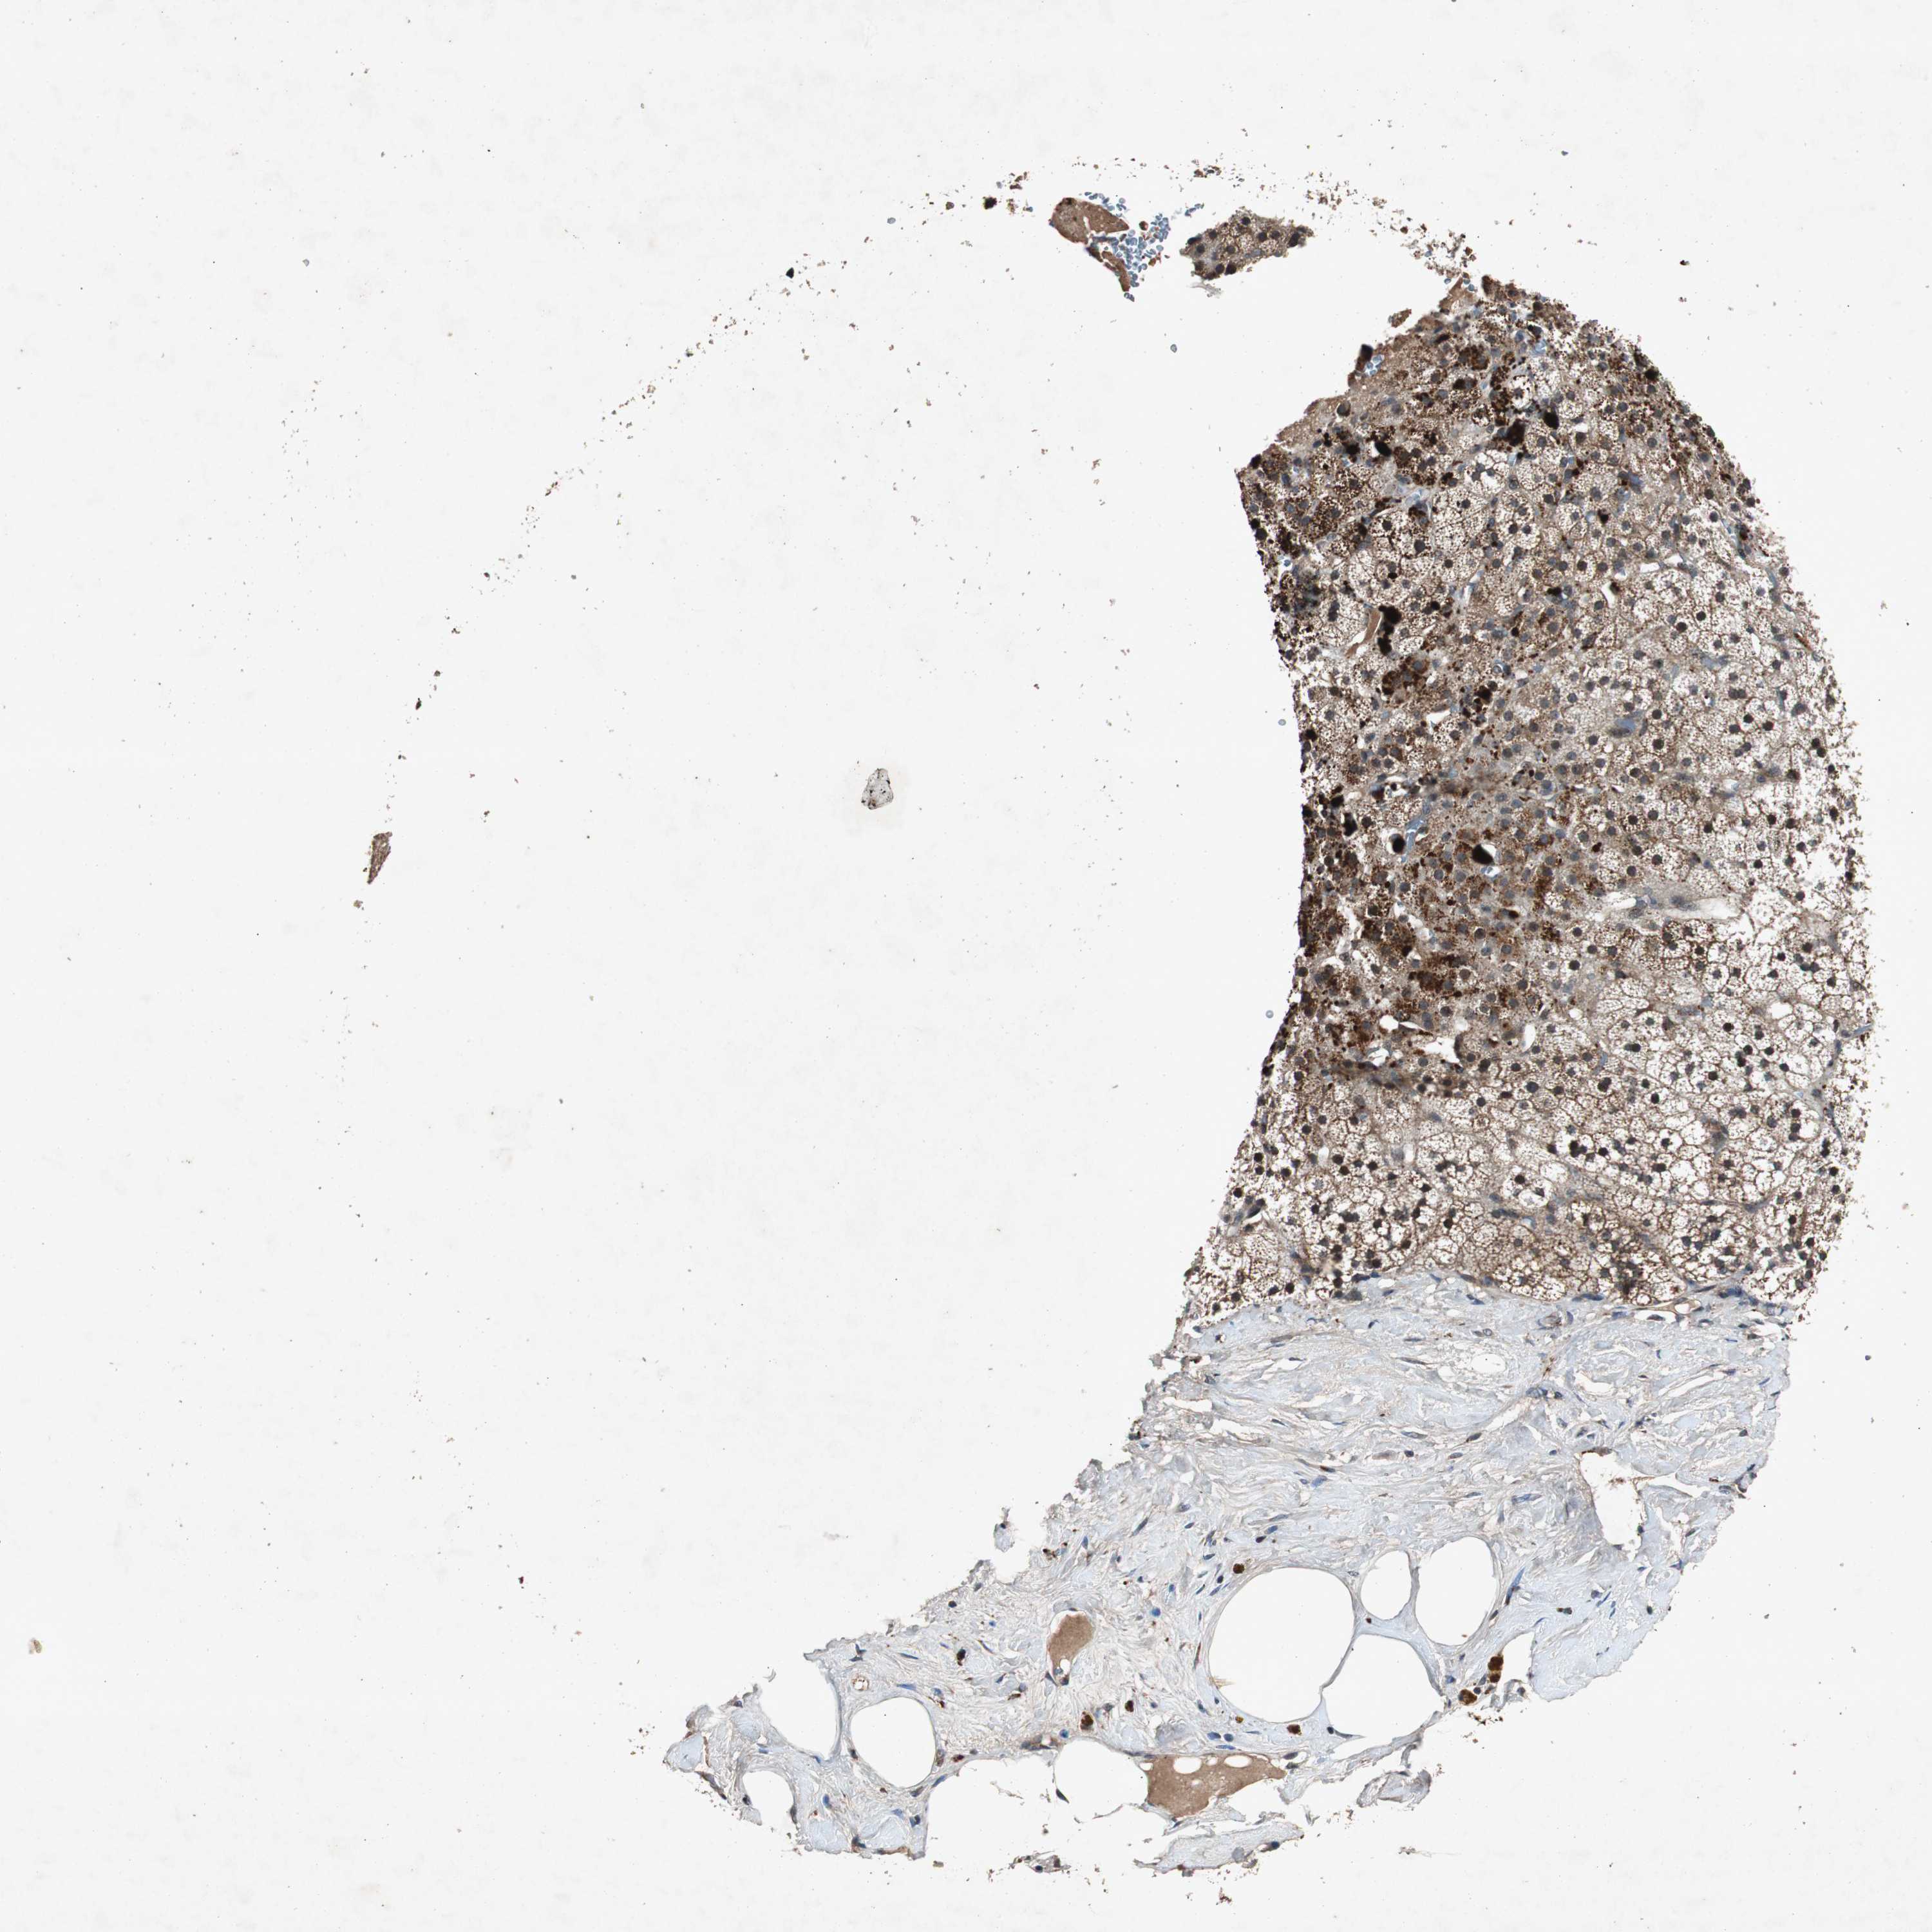

ADRENAL GLAND - Antibody stainingi

Antibody staining in the annotated cell types in the current human tissue is reported as not detected, low, medium, or high, based on conventional immunohistochemistry profiling in selected tissues. This score is based on the combination of the staining intensity and fraction of stained cells.

Each image is clickable and will lead to virtual microscopy that enables deeper exploration of all samples and also displays staining intensity scores, fraction scores and subcellular localization as well as patient and tissue information for each sample.

Antibody HPA019511Antibody HPA023088Antibody CAB007590

Glandular cells LowMediumHigh